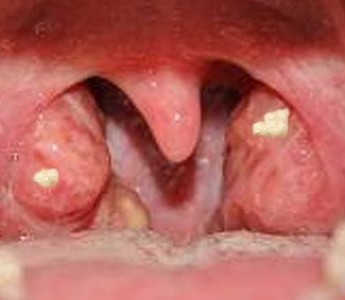

- 편도결석, 후두염, 부비강염, 기관지확장증 등의 호흡기질환 – 충치, 치아플라크, 치주염, 구강건조증 – 심리적 불안 – 위식도역류, 간질환, 신장질환

그러나 대부분은 편도결석에 의한 입냄새로 스트레스를 받고 있습니다.